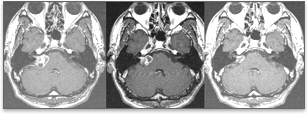

감마나이프 방사선수술의 역할은 일차적인 치료나 수술적 제거 후 남은 부위에 대한 이차적인 치료로 이용됩니다. 특히 크기가 3cm 미만의 청신경 초종에서는 수술적 치료를 대체할 수 있는 방법입니다. 청신경 초종에 있어서 정위적 방사선수술의 목적은 첫째, 종양의 성장을 장기적으로 제한하고, 둘째, 인접한 뇌신경 등의 신경 기능을 보존하며, 셋째, 치료로 인한 새로운 신경학적 합병증을 막는데 있습니다. 장기 추적에 대한 보고들에 의하면 종양 성장 억제율은 95% 이상이며 시술 전 안면신경, 삼차신경, 청신경의 기능이 보존되는 비율은 각각 95%, 90%, 60%라고 보고되었습니다. 치명적인 합병증이 없고 시술의 용이함 등을 고려하면 크기가 큰 청신경 초종이 아니라면 일차적 치료로 감마나이프 방사선 수술을 추천할 수 있습니다. 방사선 수술 후 추적 MRI 검사를 시행하면, 6~9개월 후 종양 중심부에 괴사부위가 나타나고 뒤이어 종양의 부피가 감소하게 됩니다.

위 사진들은 각각 청신경 초종의 감마나이프 수술 전, 수술 후 8개월, 13개월에 찍은 MRI로 종양이 계속 줄어들고 있음